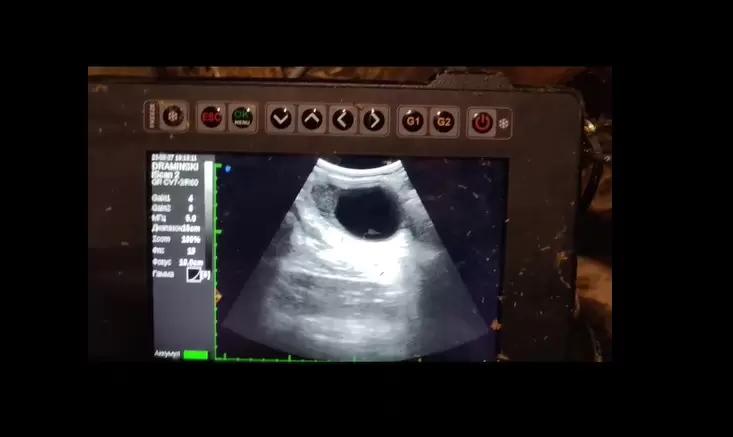

Вопросы из чатов: какая киста на УЗИ?

Замкнутая полость, образующаяся в органе в результате патологических процессов. Имеет стенку и заполнена каким-либо содержимым. В зависимости от механизма развития, структурных особенностей и локализации К. делят на ретенционные, рамолиционные, опухолевые и на К., возникающие вследствие нарушения нормального эмбрионального развития органов. По характеру выстилки внутренней стенки полости различают истинные и ложные К. Первые выстланы эпителием, реже эндотелием; у вторых стенка образована клетками той ткани, из которой они развились. Размеры, строение стенки и содержимое К. разнообразны, это связано с причиной и характером их развития, локализацией.